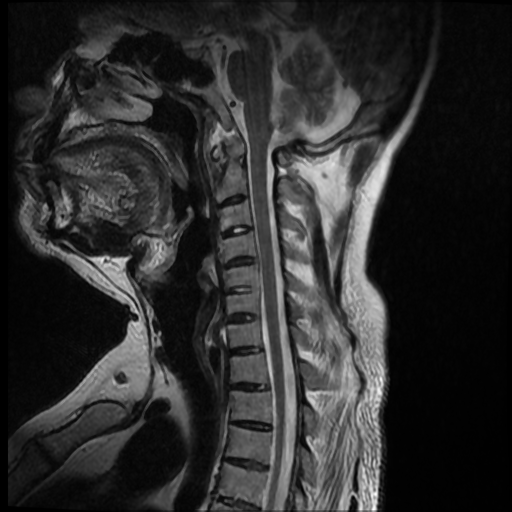

La espondilitis anquilosante (EA), es una enfermedad autoinmune inflamatoria crónica que afecta principalmente a las articulaciones de la columna vertebral y causa dolor crónico severo, afecta principalmente a las articulaciones de la columna, las articulaciones sacroilíacas y los tejidos blandos adyacentes, como los tendones y los ligamentos. En casos más avanzados, esta inflamación puede dar lugar a fibrosis y calcificación, dando como resultado la pérdida de flexibilidad y la fusión de la columna, asemejándose a un “bambú” con una posición inmóvil. Este caso se enfoca a paciente de 37 años de edad, que manifiesta rigidez y perdida de la linealidad de la columna cervical, encontrando a través del estudio de MRI calcificación de los ligamentos anterior y posterior de la columna cervical, más fusión de vértebras cervicales.

Ankylosing spondylitis (AS) is a chronic inflammatory autoimmune disease that primarily affects the joints of the spine and causes severe chronic pain. It primarily affects the joints of the spine, the sacroiliac joints, and adjacent soft tissues such as tendons. and the ligaments. In more advanced cases, this inflammation can lead to fibrosis and calcification, resulting in loss of flexibility and fusion of the spine, resembling a “bamboo” with an immobile position. This case focuses on a 37-year-old patient, who manifests rigidity and loss of linearity of the cervical spine, finding through the MRI study calcification of the anterior and posterior ligaments of the cervical spine, plus fusion of cervical vertebrae.

Paciente de 37 años de edad, no refiere trauma reciente, indica que hace mas o menos dos años inicio con dolor a nivel del cuello, y empezó a notar que el mismo se estaba inclinando hacia el lado izquierdo, esta inclinación ha ido en aumento y no le permite colocar el cuello de forma recta, causándole dolor e incomodidad. Acude a consulta y luego de ser evaluado por facultativo le solicitan estudio de resonancia magnética de columna cervical.

Se observa perdida de la lordosis normal de la columna cervical.

Se observa hipo intensidad del ligamento longitudinal anterior y posterior de la columna cervical, también se observa perdida de la movilidad y rigidez de la misma, los ligamentos interespinosos se ven hipointensos en T2 y en T1, al igual que el pliegue nucal, lo que sugiere calcificación de estas estructuras anatómicas.

Se observa fusión de las vertebras cervicales 5-6 y 6-7, dando la apariencia de bambú.

• Perdida de la lordosis

• Ligamentos espinales anterior, posterior, interespinosos y pliegue nucal calcificados

• Fusión de vertebras cervicales 5-6 y 6-7.